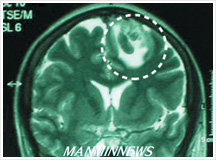

Deaconess Young-shim Lee, healed of cerebral hemorrhage without any medical treatment / Before receiving prayer / After receiving prayer